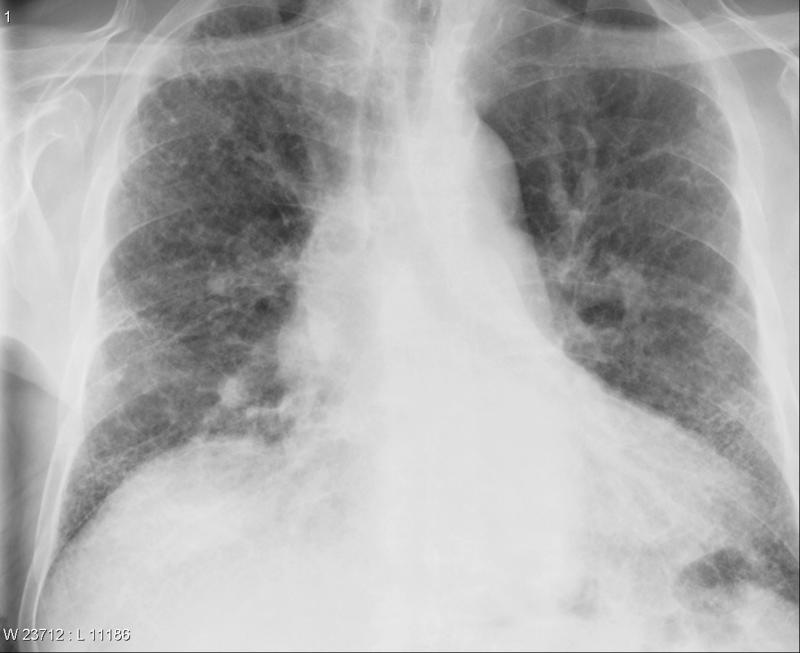

Gallery Pulmonary Fibrosis IPF Case 4a

Case 4a